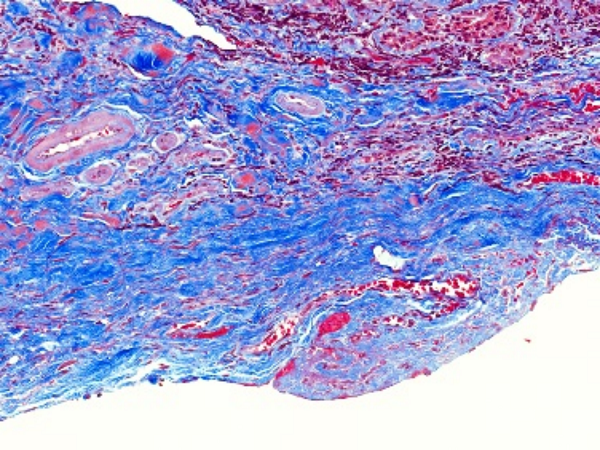

MASSON染色利用不同染料分子與組織結(jié)構(gòu)的相互作用,實(shí)現(xiàn)對膠原纖維和肌纖維的精準(zhǔn)區(qū)分。在染色過程中,肌纖維呈現(xiàn)為紅色,而膠原纖維則呈現(xiàn)為綠色或藍(lán)色。這種色彩對比使得纖維組織在顯微鏡下變得清晰可見,醫(yī)生能夠清晰地觀察到纖維化的程度和范圍。

圖1. Masson組織染色結(jié)果示例(最右列),可看到不同處理?xiàng)l件下膠原纖維(藍(lán)色)和肌纖維(紅色)的分布不同

②纖維化組織染色結(jié)果

在纖維化組織中,MASSON染色會(huì)呈現(xiàn)出明顯的紅色或紫色區(qū)域。這些區(qū)域代表了膠原纖維的增生和沉積,是纖維化病變的典型表現(xiàn)。通過觀察這些區(qū)域的分布和范圍,可以初步判斷纖維化的程度和范圍。

③纖維化程度評估

根據(jù)MASSON染色結(jié)果,我們可以對纖維化程度進(jìn)行初步評估。一般來說,紅色或紫色區(qū)域越多、越密集,說明纖維化程度越嚴(yán)重。同時(shí),還可以結(jié)合其他病理特征,如纖維束的粗細(xì)、排列方向等,進(jìn)行更全面的評估